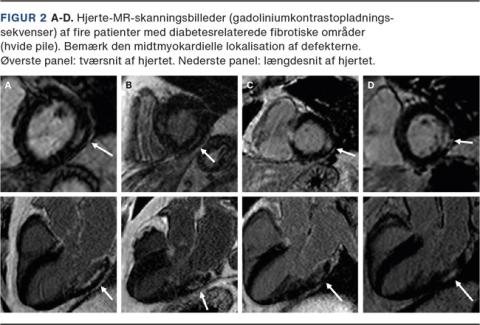

Historisk var det den danske læge Knud Lundbæk, der i 1954 beskrev de særegne diabetiske karforandringer ved DM [22], og det var også Lundbæk, der i 1969 foreslog, at DM måske gav ophav til en egentlig »diabetisk kardiomyopati« [23]. I 1970’erne viste flere mindre patologistudier af patienter, der havde DM og døde med tegn på inkompenseret hjertesygdom, at HF kunne være associeret med stive hjerter med udbredt fibrosedannelse og ophobning af »avancerede glykerede endeprodukter« (AGEs) [24]. Nogle af patienterne have deciderede »øer af fibrose«, der ikke var relateret til IHD [24], idet deres koronararterier var uden signifikant aterosklerose, og fibrosedannelse ved IHD altid udgår fra subendokardiet, hvor de fibrotiske øer hos patienterne med DM var lokaliseret midtmyokardielt. Lundbæk havde altså ret: DM giver ophav til en specifik kardiomyopati, der ikke behøver at være associeret til IHD. Disse studier er i dag vidtgående glemt, men forståelsen af, at DM giver anledning til diffus fibrosedannelse af myokardiet, udtyndede koronararterier (et fund, der også kendes fra koronarangiografier af patienter med DM) og stive hypertrofiske ventrikler, er nu velkendt.

Patienterne havde begyndende tegn på diastolisk dysfunktion med øget E/e’ (gennemsnitligt 9,9 (spændvidde: 8,7-12,6)) hos patienter, der havde T2DM og fibrose, og 8,8 (7,4-10,7) hos patienter, som havde T2DM uden fibrose, og nedsat maksimal fyldningshastighed af LV (peak filling-rate/end-diastolisk volumen i LV gennemsnitligt 2,3/s (standardafvigelse (SD): ± 0,6) hos patienter med T2DM og fibrose vs. 2,9/s (SD: ± 0,6) hos raske kontrolpersoner. Særligt patienterne med fibroseøer har høje værdier af E/e’ og også større LA-volumen og høje værdier af natriuretiske peptider, der i andre studier er påvist at korrelere med udvikling af HFpEF. Det er ofte patienter med lav maksimal myokardiegennemblødning, der også har høj ECV, men en sikker tidsfølge har endnu ikke kunnet bestemmes, og det er stadig usikkert, hvilken af de to fænotypiske manifestationer af T2DM der har størst betydning for senere udvikling af HFpEF. Det synes, som om nedsat maksimal gennemblødning og øget forekomst af fibrose begge påvirker den diastoliske funktion (E/e’), og det synes også, som om fibrose og nedsat gennemblødning gør det ad veje, som er uafhængige af hinanden (nedsat relaksation vs. nedsat LV-diastase). Histologiske studier viser, at AGE-bundet kollagen initialt omskeder de små kar [10], og det er sandsynligt, at det er fibrose, der »kommer først« og nedsætter myokardiets karvitalitet, men hypertension kan i sig selv udtynde kar og give anledning til mindre mængder fibrose [29], og det er derfor lige så muligt, at den relative iskæmi, som denne småkarssygdom nu afstedkommer, giver yderligere fibrosedannelse.